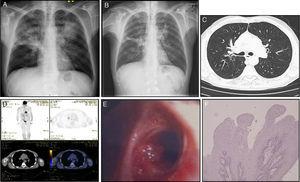

He had recent complaints of productive cough and minor bleeding sputum. Physical examination was unremarkable and routine blood sample analysis was normal. Chest X-ray showed significant improvements when compared to the initial abnormal findings, but showed a linear opacity at the horizontal fissure of the right lung and a heterogeneous and poorly defined opacity located above the left hilum. Chest computed tomography described fibrotic lesions at the upper right lobe, diffuse thickened bronchial walls and small bronchiectasis in the anterior segment of the upper left lobe. Positron-emission tomography reported a mild increase of metabolic activity in the right hilum region. Videobronchoscopy revealed a bleeding cauliflower lesion on the posterior segment of the right upper bronchus and minor hematic secretions. Bronchial biopsies disclosed bronchial squamous papilloma with moderate metaplasia, cellular atypia and moderate dysplasia of the respiratory epithelium (Figure 1).

Figure 1. Chest X-ray before (A) and after (B) antibiotic treatment for pneumococci pneumonia. (C) Computed tomography scan showing diffuse thickened bronchial walls and small bronchiectasis in the upper left lobe. (D) Positron-emission tomography/Computed tomography with 18-fludeoxyglucose (FDG) displaying increased metabolic activity in the right hilum region. On bronchoscopic examination (E), a cauliflower lesion was observed on the posterior segment of the right upper bronchus. (F) High-power microscopic appearance of fibrovascular cores surrounded by squamous epithelium (original magnification 100×, haematoxylin and eosin stain).